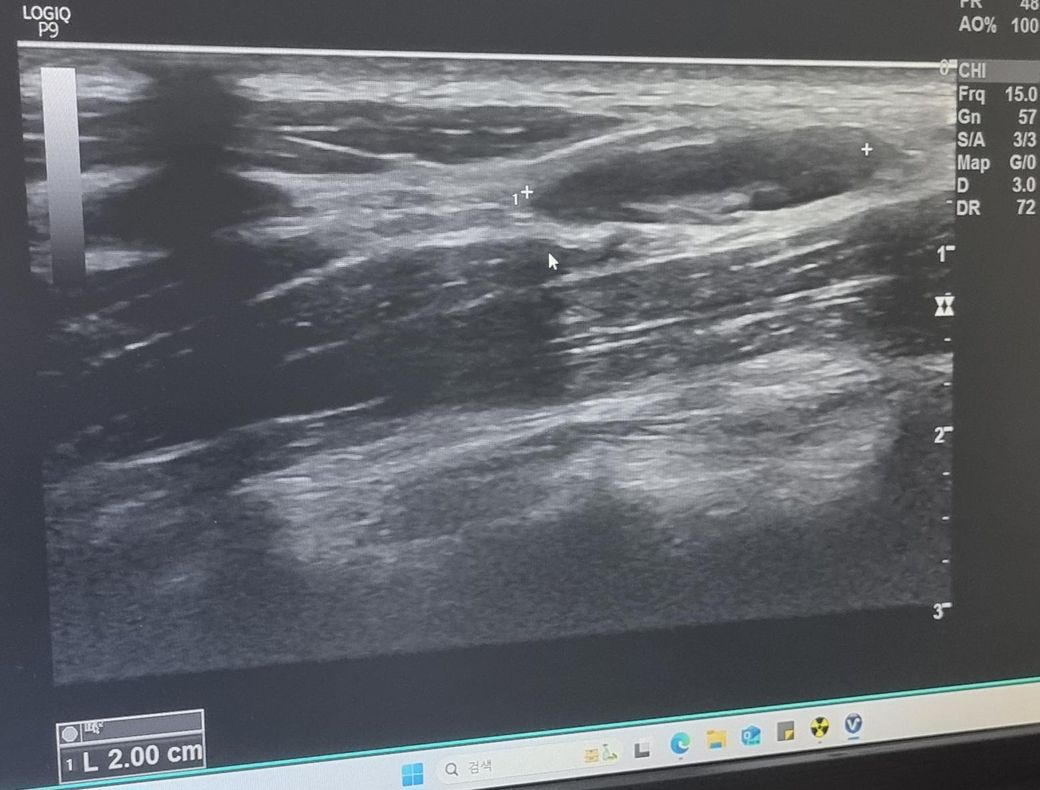

한 달 넘게 멍울 만져져서 초음파 받았는데 크기가 좀 커서요 괜찮나요? 궁금합니다 ㅜㅜ V5 구역입니다.

초음파 사진 괜찮나요 ㅜㅜ?